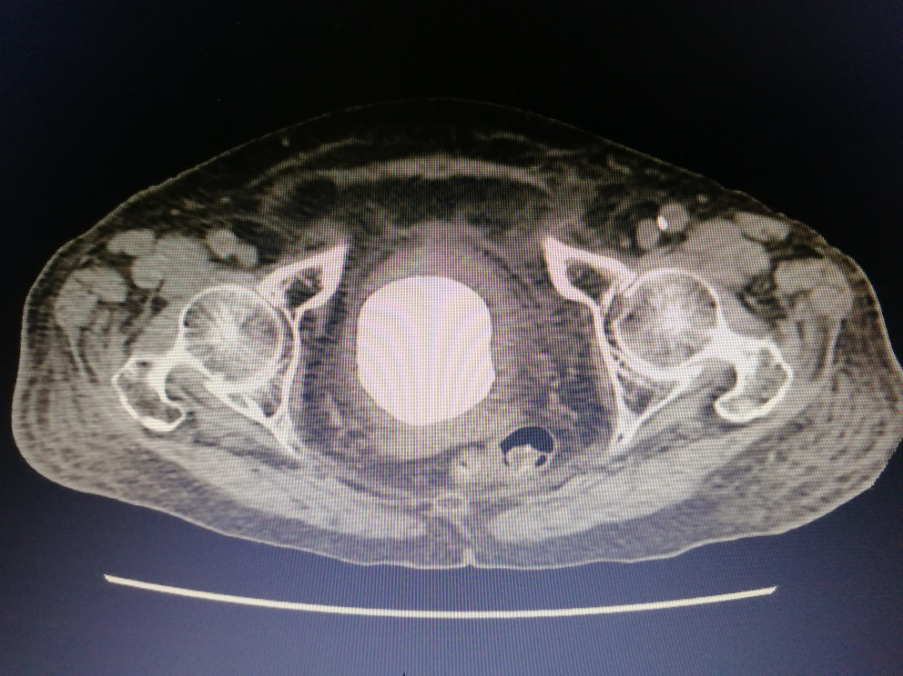

入院后,经过专业的全面系统检查后,我院泌尿外科专家组针对李老太病情召开了联合会诊。李老太的结石犹如鹅蛋般大小,而且已引起一系列严重并发症,不及时取出结石将造成更严重后果,对于一个91岁高龄而且身体情况欠佳的老太太来说采取哪种手术方案都有弊有利。

暨南大附属一院泌尿外科卓育敏主任分析:“为她选择治疗方案的时候必须慎重,因患者年龄大,多项器官功能都有明显衰退而且膀胱已无多少操作空间,开放手术虽很快可以完成,但一个7-8公分的伤口对她来说就是一个很大的创伤,很容易发生脂肪液化,尿漏等并发症,这对老人都可能造成不可预测的影响。而采用经尿道手术近乎无创,但这种结石最坚硬,又那么大,手术时间肯定很长,医生累且不说,一台高功率碎石机连续多小时的工作可能都扛不住会死机,要准备2台机器轮番上阵,要避免器械对老太膀胱黏膜损伤。”

此外,患者腰椎处压缩骨折,骨质疏松严重,心肺功能差,对麻醉的选择也是一种考验。专家团队仔细分析后,决定给老太太行细针硬外麻经尿道肾镜钬激光膀胱碎石取石术。一根纤细的纤维肾镜轻松地进入了老太太的膀胱,可以见到膀胱内的巨大结石与膀胱壁几乎紧密接触,找到缝隙后一点一点逐步击碎结石,将结石粉末化处理,并用吸引器将膀胱内碎石多次吸出,反复多次,最终将结石干净彻底清楚。手术圆满成功,手术进行了近4个小时,患者术中情况生命体征都很稳定。